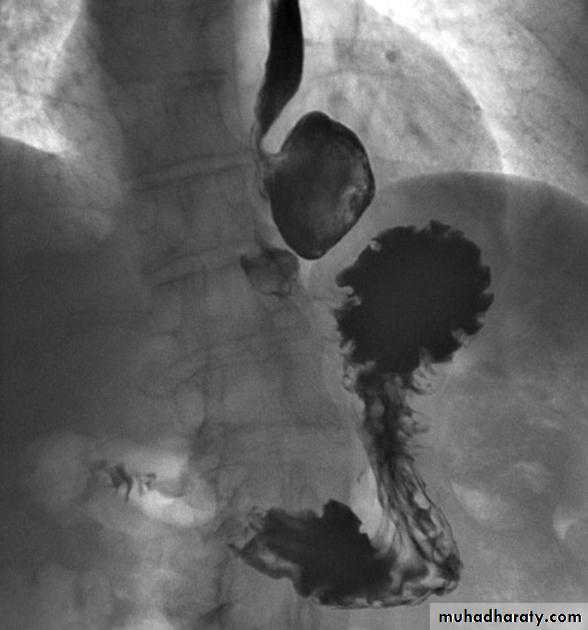

Esophageal diseases

Webs

Majority protrude from anterior esophageal wall

short, thin web (arrows) with minimal intraluminal extension.